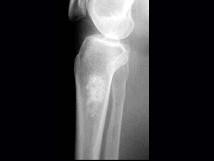

问题 女,年龄47岁,膝关节疼痛6月余,曾服用泼尼松(服用时间5个月),有骨性关节炎史,结合图像,最可能诊断是?(?)

选项 A.慢性化脓性骨髓炎 B.骨梗死 C.恶性骨肿瘤 D.内生软骨瘤 E.骨纤维结构不良

答案 B